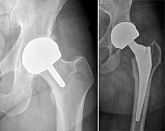

Еndoprosthesis of hip joint

In the late stages of arthrosis of the hip joint, medial fractures of the femoral neck in the older age group, the only way to recover is to replace the affected joint with an artificial joint - arthroplasty.

This method allows you to return the limb's limb, the full volume of movements in the affected joint, to save from constant pain and crunch during movements and, as a consequence, to return the patient to a full active life.

Below are presented X-ray photographs and photographs, illustrating the amount of motion in the affected joint before and after surgery.